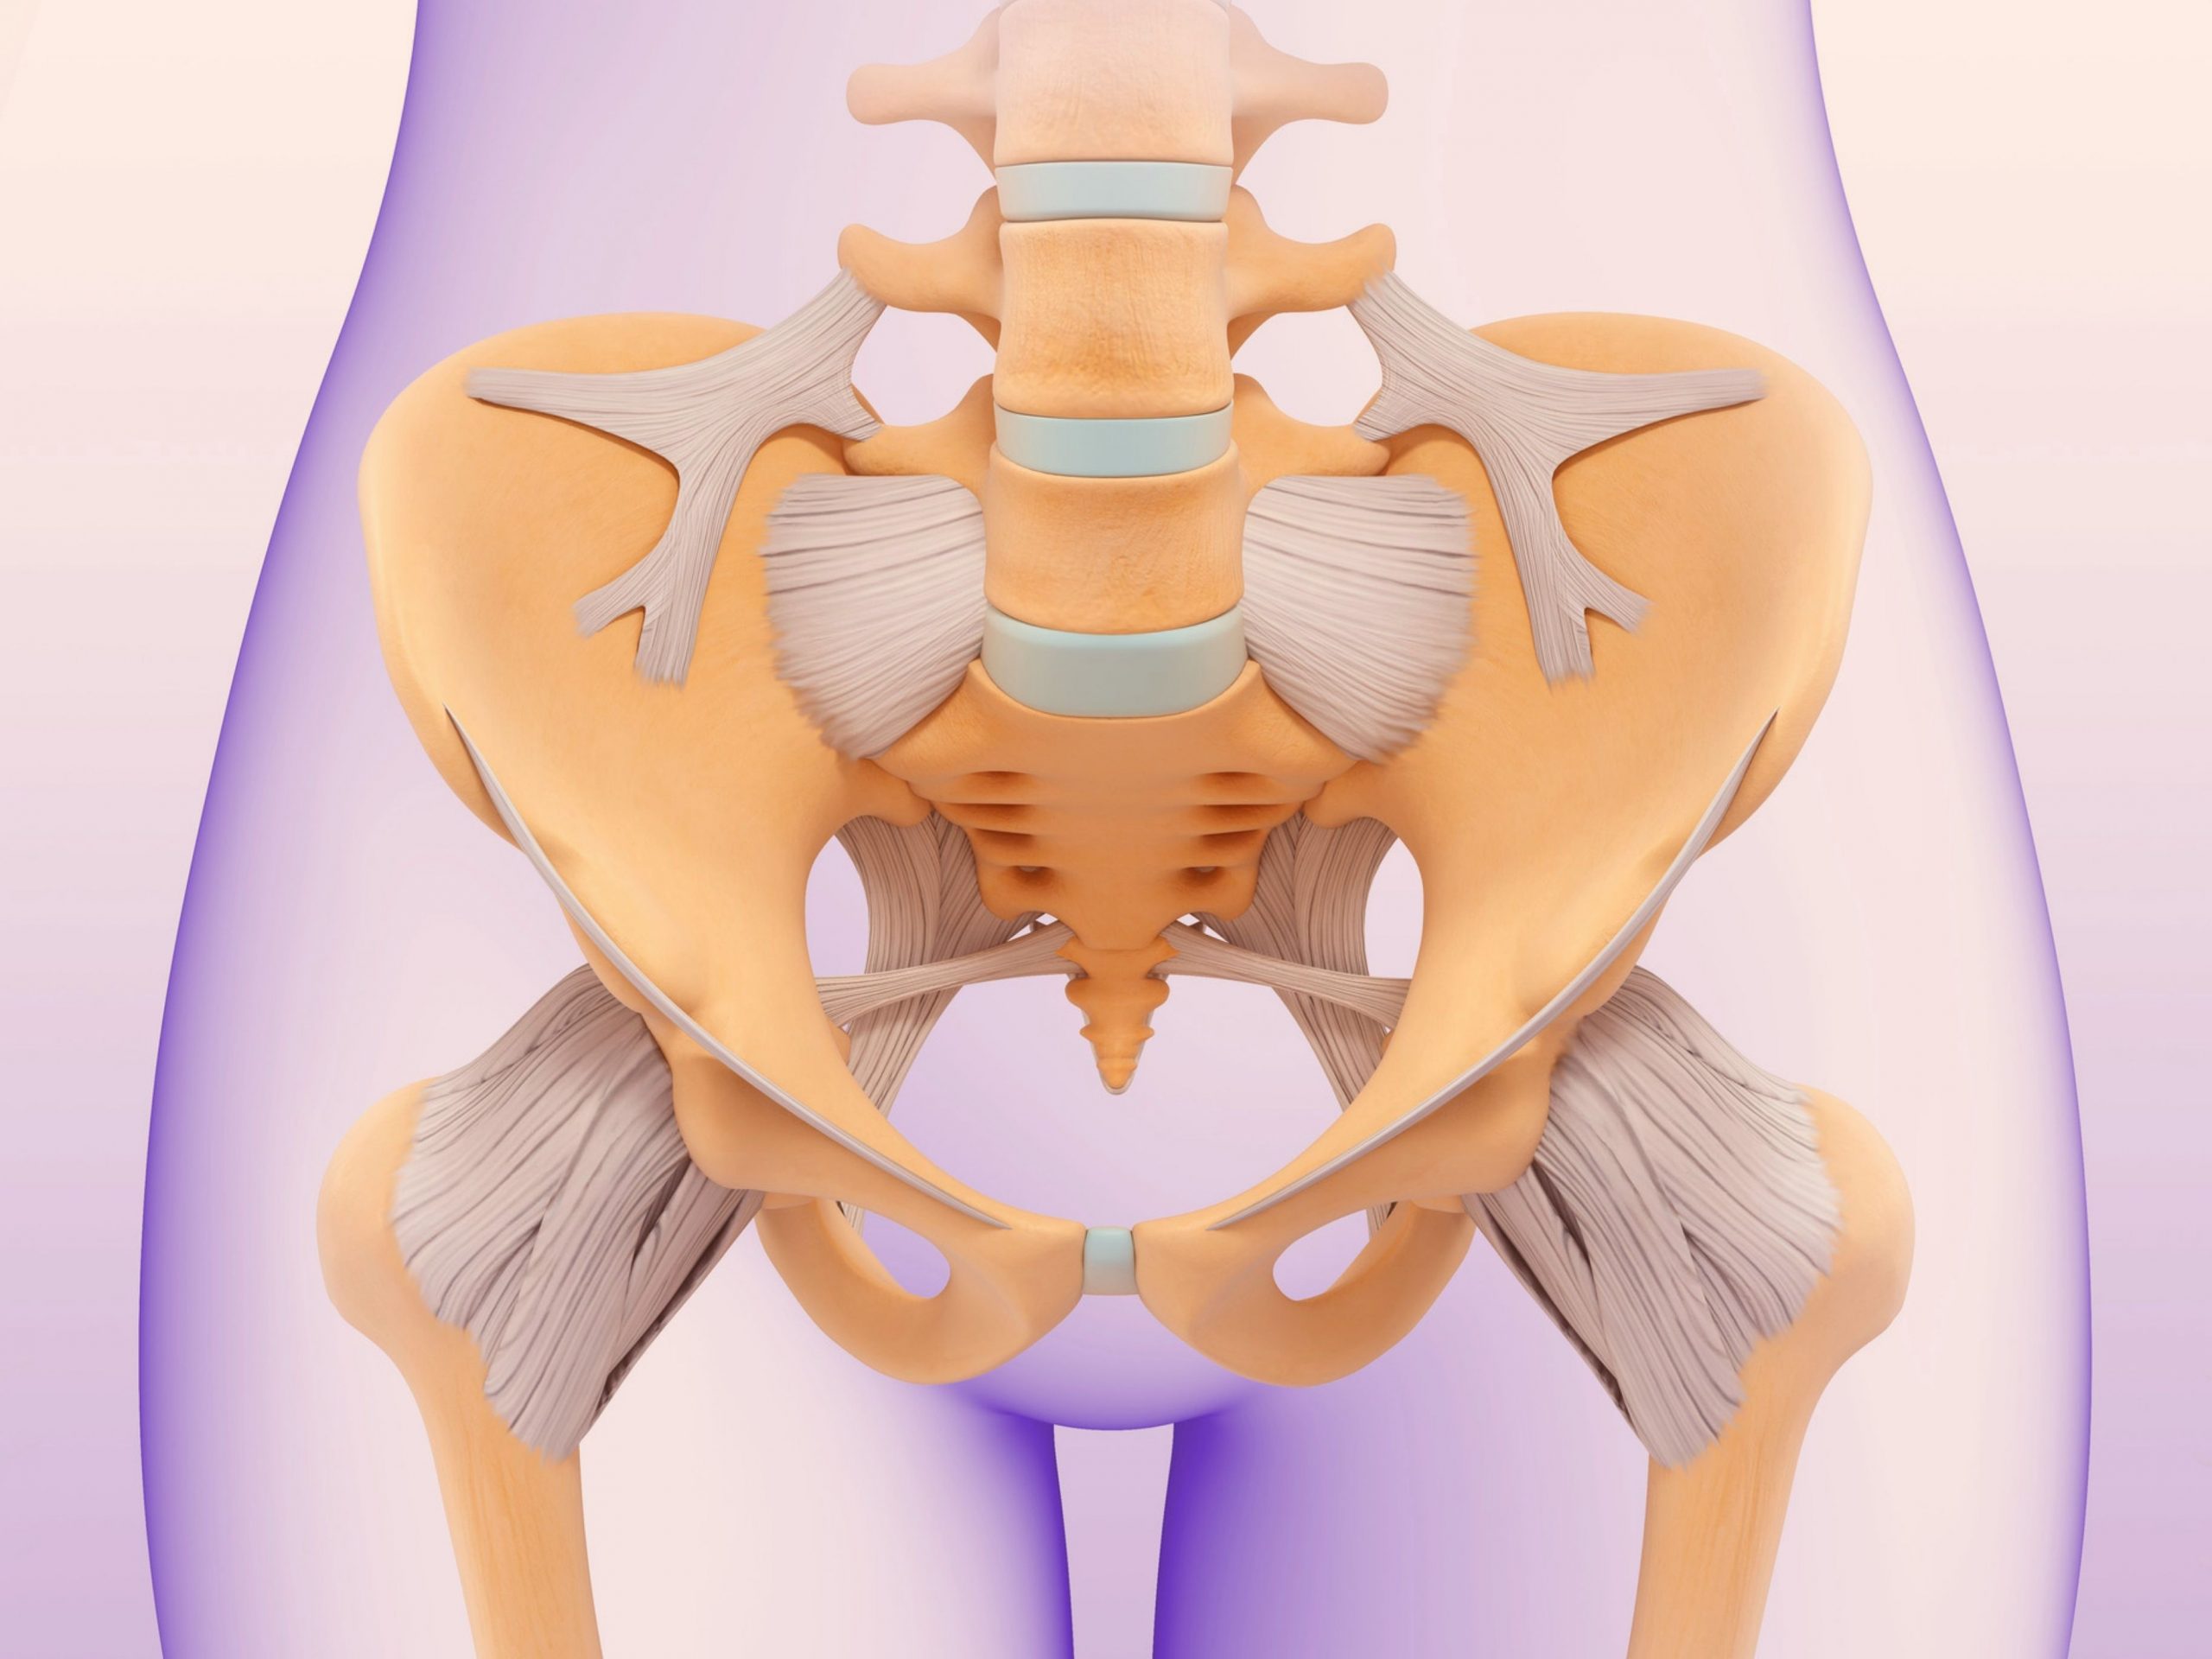

Анатомия малого таза: детальные схемы и изображения